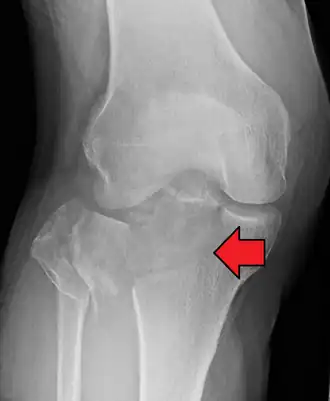

Fractura de meseta tibial leve en vista con Rayos X AP en la rodilla -

Una fractura de meseta tibial vista con rayos-X